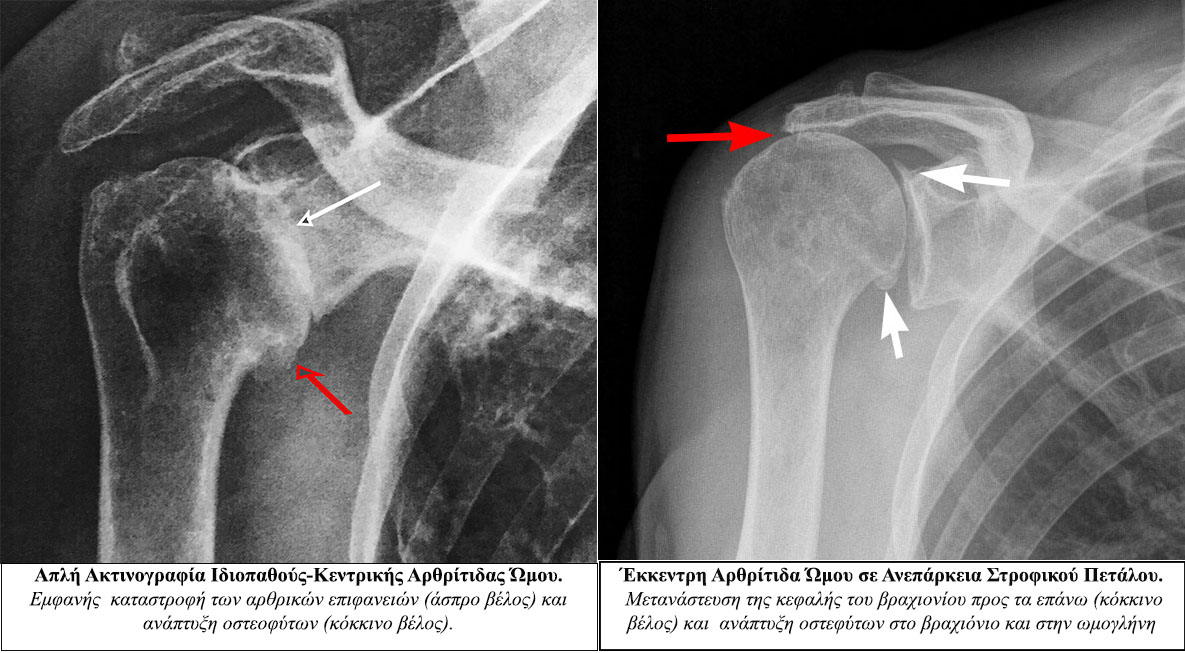

Είναι η αλλοίωση-καταστροφή του αρθρικού χόνδρου που οδηγεί τελικά σε πλήρη αποδιοργάνωση της άρθρωσης.

Η διάγνωση της αρθρίτιδας του ώμου στηρίζεται κυρίως στα εξής: